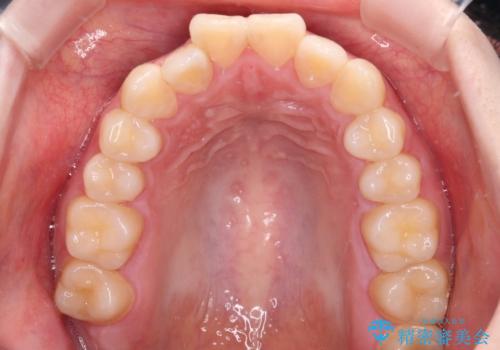

強い舌の突出癖により、上下前歯が前方に飛び出しており、特に上顎前歯は下顎よりも更に前方に位置している状態でした。

上顎前歯をしっかりと後方に移動させるため、口蓋側にアンカースクリューと補助装置を併用し、上下左右の第一小臼歯4本を抜歯し、ワイヤー装置にて矯正治療を行うこととしました。

口元の突出感が改善されてことで、下唇に引っかかっていた上顎前歯も気にならなくなりました。